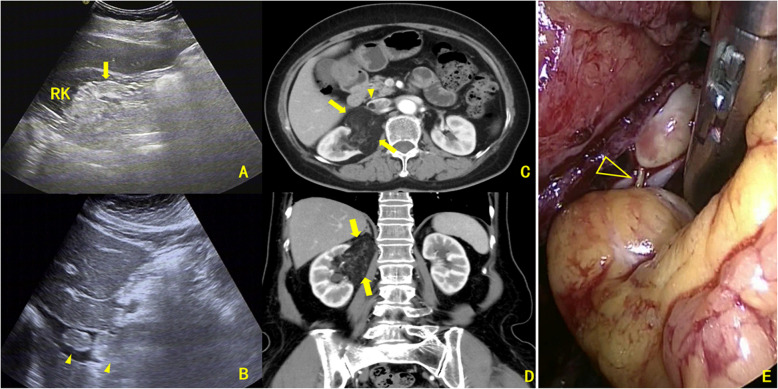

Results: Enhanced CT showed renal sinus involvement in all CAML cases versus four ccRCC cases (p = 0.002). All primary CAML tumors had fatty components, compared to one ccRCC case (p < 0.001). Enhanced CT also revealed 7 VTTs with fatty components (6 in the CAML group) (p < 0.001). Thrombus lengths in the inferior vena cava (IVC) were 8.05 ± 2.22 cm for CAML and 5.29 ± 2.38 cm for ccRCC, with no significant difference (p = 0.610). The maximum/minimum anteroposterior VTT diameter ratios were 3.98 and 1.09, respectively (p < 0.001); coronal diameter ratios were 4.00 and 1.12, respectively (p < 0.001). Ultrasound revealed that, except for one Mayo Level 0 case, the involved IVC in the CAML group had continuous, intact walls with blood flow signals in the residual lumen, while in the ccRCC group, most VTTs had unclear boundaries and only one case showed blood flow signals in the residual lumen (p = 0.001). Intraoperative blood loss was significantly lower in CAML cases (p = 0.017). No CAML patient had VTT invading the venous wall, unlike 8 ccRCC patients (p = 0.016). All patients were followed for 21-74 months (median: 34.5 months, mean: 36.6 months). All were alive with normal renal function, and no tumor recurrence or metastasis was observed.

Conclusion: Renal CAML with VTT is characterized by three imaging features: the presence of fatty components, a unique geometric growth pattern, and the absence of venous wall invasion, potentially serving as valuable indicators for differentiating CAML from ccRCC lesions.